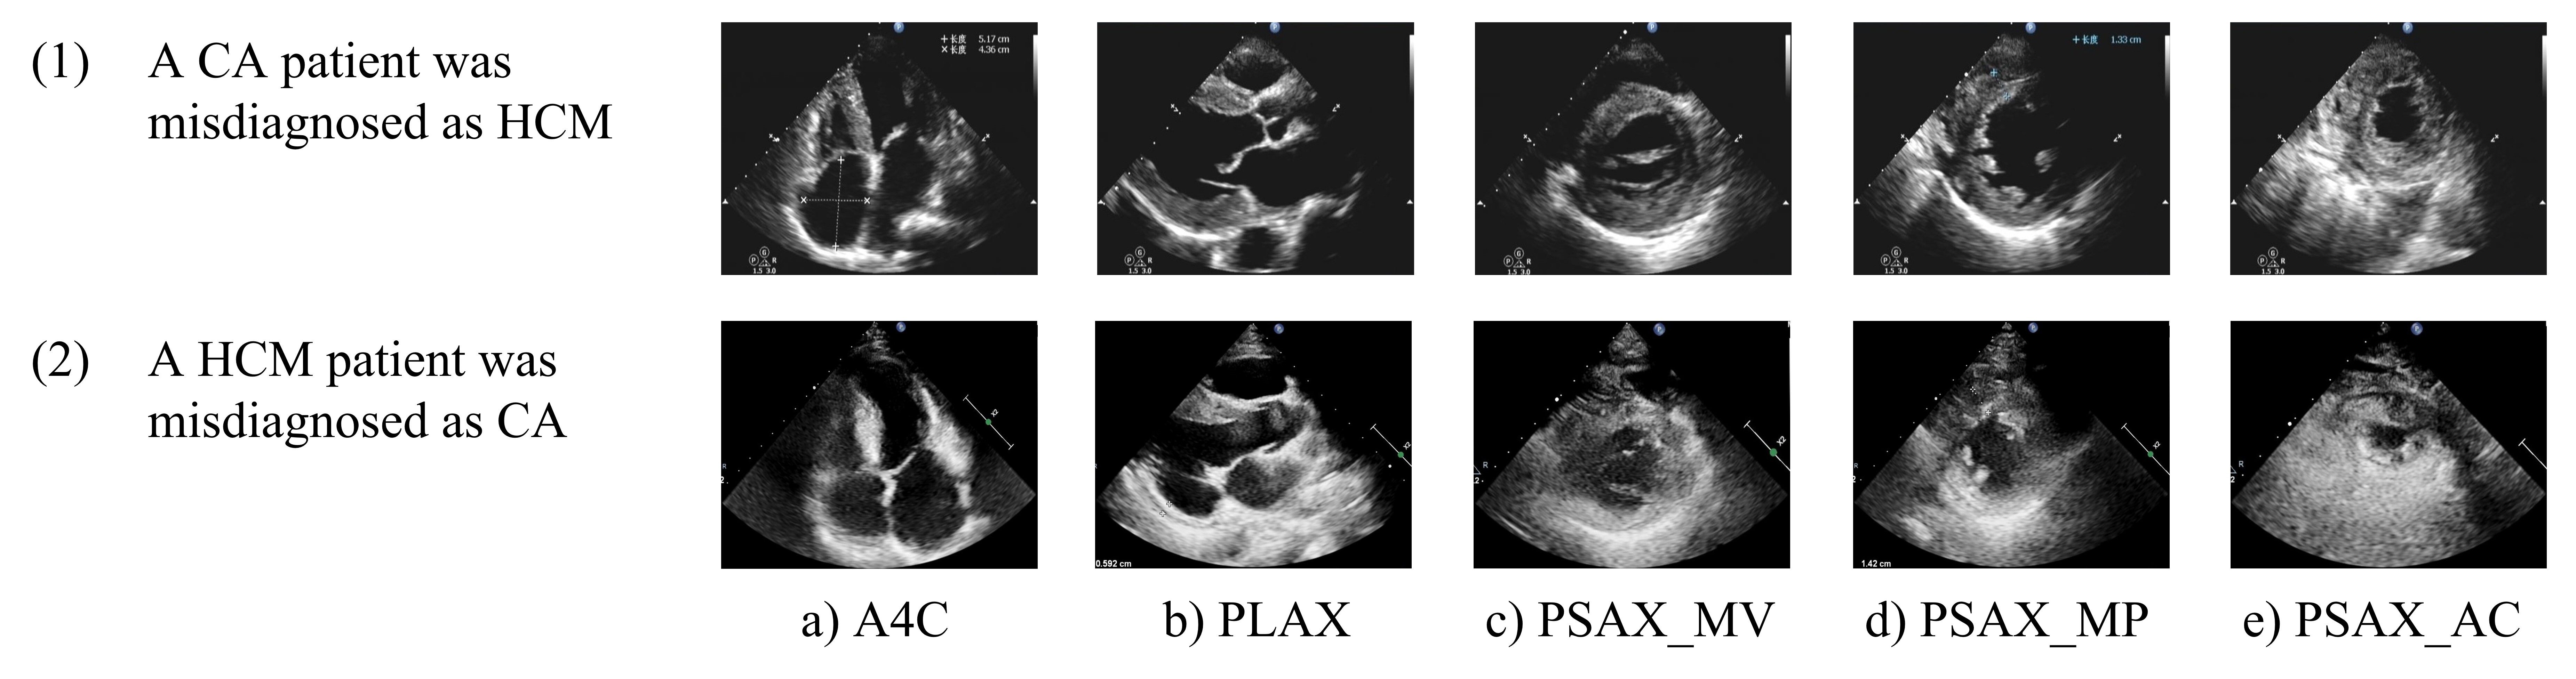

In our experimental results, we also identified three cases of CA patients misdiagnosed as having HCM based on echocardiography images. Examination of these images revealed distinct characteristics contributing to these misdiagnoses. For instance, as observed in Fig. 9, misdiagnosed CA patients exhibited low image gain, poor recognition of myocardial echo features, and thickened myocardium. Conversely, another patient with HCM was misdiagnosed as having CA due to excessively high image gain, poor image quality, and significant echo noise in the myocardium, resulting in an unclear display of the myocardial boundary. Our study yielded an accuracy rate of 0.905 in identifying HCM and CA based on static 5-view echocardiography images, which is competitive compared to diagnoses made by senior sonographers. Referring to the work of Yu et al. [bib0], our study further selected specific views, including PSAX_MV and PSAX_MP and PSAX_AC, to better reflect the differences between HCM and CA in terms of myocardial echo, thickness, distribution, and pericardial condition. However, as demonstrated by the misdiagnosed cases, slight differences in echocardiography may affect the differentiation between the two conditions.

Refer to caption

Figure 9: Examples of misdiagnosed patients. (1) is five views of a CA patient misdiagnosed as HCM, while (2) is five views of a HCM patient misdiagnosed as CA.